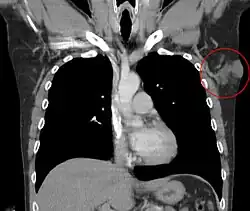

El dermatofibrosarcoma protuberans comienza como una zona pequeña y firme en piel y comúnmente tiene un diámetro de 1 a 5 cm. Es un tumor que crece lento y por lo general se encuentra en el torso, pero también se puede encontrar en los brazos, las piernas, la cabeza y el cuello.[5] Alrededor del 90% de DFSPs son sarcomas de bajo grado. Alrededor del 10% son mixtos; que contienen un componente sarcomatoso de alto grado (DFSP-FS); por lo tanto, se considera que son sarcomas de grado intermedio. DFSPs rara vez conduce a una metástasis (menos del 5% se hacen metástasis), pero DFSPs puede recurrir localmente. DFSPs surgen en los pacientes que están en sus treinta años, pero a veces se han visto en niños o ancianos.